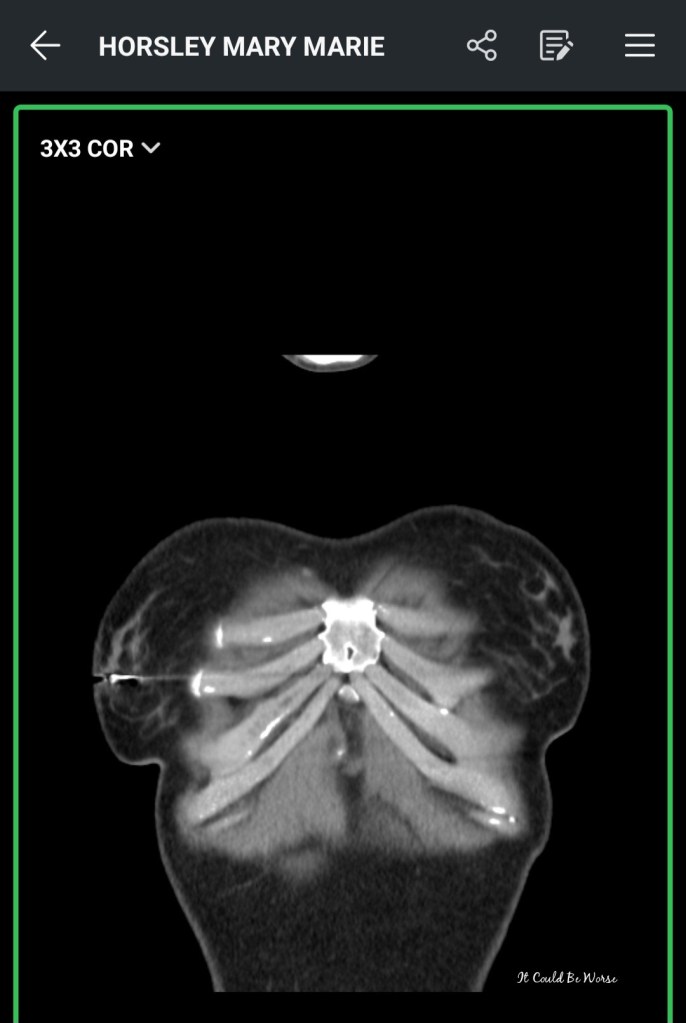

I am around 10 months post-op for my last (my 7th) Slipping Rib Syndrome surgery. I have had some pain, clicking, and grinding in my upper ribs and had to get a separate CT scan for my follow-up with Dr. Hansen.

Now, my last repair looks fine but after seeing my CT scans, Dr. Hansen said he had miscounted some of my ribs – so my repair did not happen to my 8/9/10 ribs but rather my 7/8/9 area.

This happened because my 12 ribs are tiny. Like really, really small. So, they were missed when getting hands-on and counting my ribs. My 10th ribs on both sides are both free-floating, hanging low and almost acting as the 11th ribs, and the 11th ribs acting as 12s. These lower floating ribs haven’t caused too many issues – I may feel back pain where my 11th ribs are so close to my 12s, but I notice more pain in my upper ribs than my lower.

Dr. H thought I possibly had a bridging cartilage fracture at rib 5/6 – and he was right, my bridging cartilage is mildly separated, but not fully yet. We discussed excising the bridging cartilage area but Dr. H fears that that could lead to lower chest wall instability with my wonky ribs because they look weakly attached to my sternum.

In the image below, it shows you the bridging cartilage area. Mine is on the opposite side.

So, we discussed starting small with a nerve ablation for the rib 5 area with a pain management specialist. Now, this isn’t a permanent fix and the nerve may very well grow back and I have to repeat the process – it may help the nerve pains but I may be stuck with the rib clicking and grinding feeling forever.

But, if it fails, Dr. H and I will re-entertain the bridging cartilage excision route after going the ablation route first.